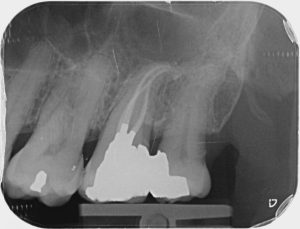

Clinical Cases